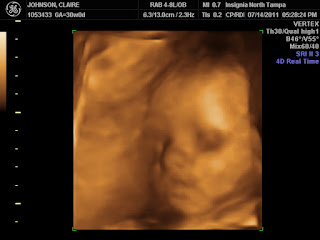

When these ultrasound pictures were taken, I was 30 weeks. We had both of our moms there, and Amy got to come, too. It's so cool to get this glimpse of what the baby looks like. So much better than the traditional sonogram (although those are exciting, too). We thought that Emery is going to look a lot like Ava. But I am starting to see a combination of the two of us, which is what I would want, anyway. Of course, until we see her in person, I guess we still won't know for sure. I love this last picture, where she's smiling. Jason is hoping that means that she will be lighthearted. I guess we'll see.